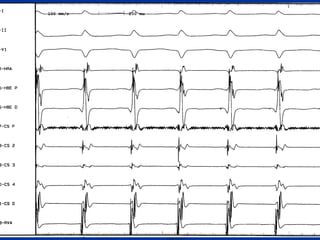

Intracardiac Electrocardiography (EPS) of

WCT

Basic EPS

--Identifies whether broad-complexIdentifies whether broad-complex

tachycardias are ventricular ortachycardias are ventricular or

supraventricular in origin:supraventricular in origin:

which is the leading the atrium or thewhich is the leading the atrium or the

ventricle ?!ventricle ?!

During the CulpritDuring the Culprit

arrhythmiaarrhythmia?!

Fahmy T, Hammouda M, Mokhtar M, 2001